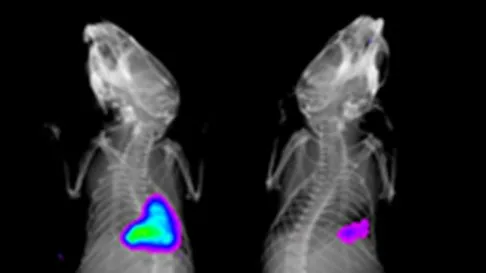

Optical image of mouse cathepsin

Cathepsin sensitive probe in mice with lung injury in untreated  (A) and treated (B). Images courtesy of Dr Kev Dhaliwal, CIR,QMRI.